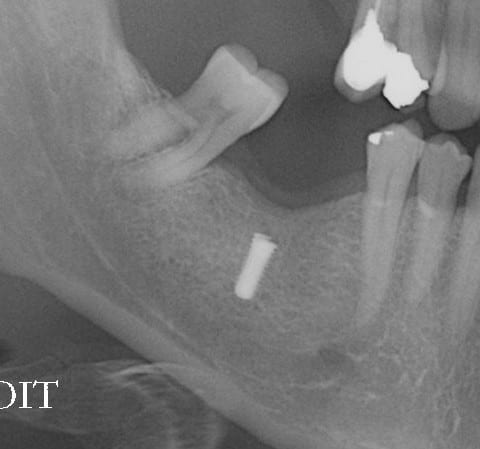

Je n'ai pas encore prescrit de SCAN,

j'ai juste une pano, mais rien de spécial dessus, implant cylindrique, à vue d'oeil, diam 4, long 10 à 12 mm.

un scan?

Je n'ai pas de Scan.

je l'ai vue cet AM, je n'ai pas encore fait de prescription.